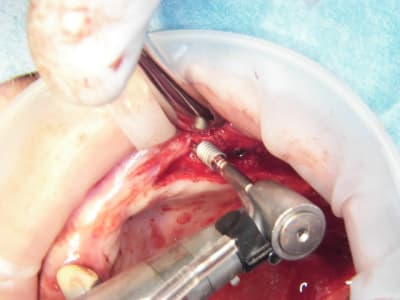

et puis alors??? on a un confrère qui s'éclate dans son travail et qui nous communique sa joie, en plus de photos qui nous apprennent beaucoup sur sa technique....c'est mieux que des posts du genre "j'en ai mare" ou " je flippe" ou encore "donnez moi une corde pour que je me pende..." , non???

pxav fait partie de ceux là...il nous en à fait à plusieurs reprises la démonstration avec ses techniques d'expansion osseuses extrêmement intéressantes...

15/07/2009 à 21h13

Pose d'implant court ce qui n'est pas ma tasse de thé, mais il ne faut pas mourir idiot, alors.

Un 103.4, un 6.5x4.6, un 8x4.6 et un 8x3.4

Première pour moi avec le nouvel Axiom d'Anthogyr.

Je n'étais pas sur de pouvoir utiliser la technique avec implant lisses, mais si.

Implants légèrement coniques, autoforants, outils trilobé et non pas 8 pans creux.

Pas eu de problèmes particuliers, il faut attendre pour le résultat.

Seul point il faut faire attention au vissage qui conditionne la position du cône morse.

Globalement j'ai bien aimé, même si je n'ai pas été aussi fabuleusement génial que d'ab dans la réalisation..........

Merci pour cette expérience partagée. Belles photos. Merci aussi d'avoir l'honnêteté de présenter un cas qui ,s'il paraît franchement parfait sur les photos de chir, l'est un poil moins sur la pano (mais c'est qu'une pano). De toute façon avec une expérience comme la tienne la gestion prothétique se fera sans doute sans trop de soucis.